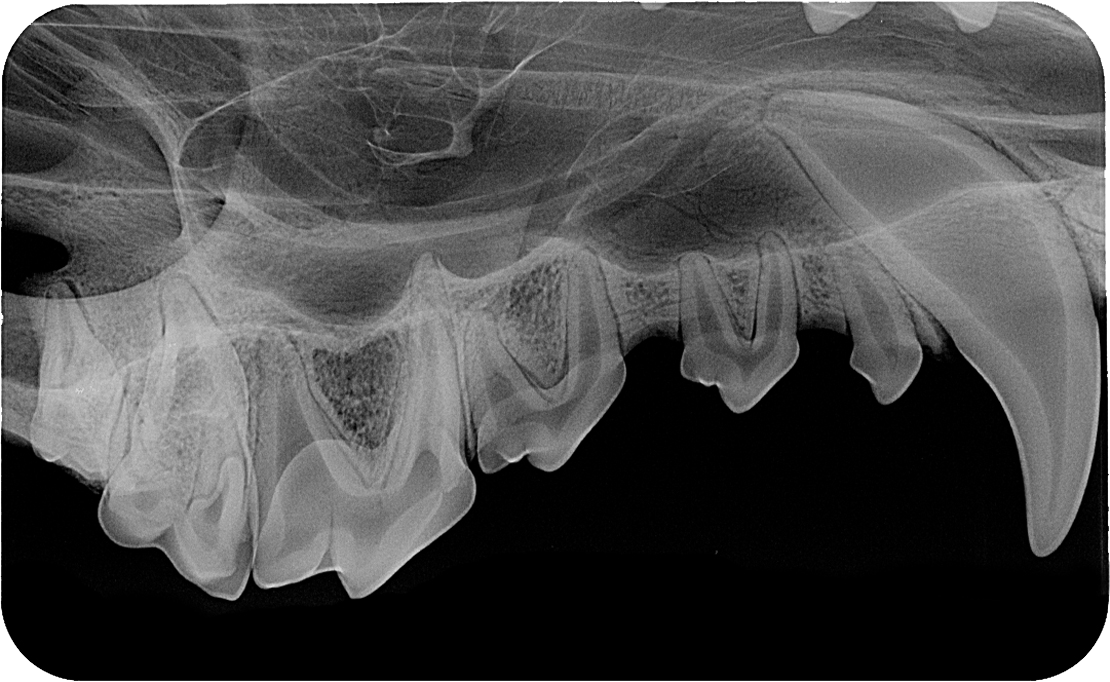

Innovativer Speicherfolienscanner für alle intraoralen Formate. Der außerordentlich kompakte Speicherfolienscanner CR 7 VET wurde speziell für die intraorale Röntgendiagnostik in der Veterinärmedizin entwickelt. Das Gerät verarbeitet alle üblichen Kleinformate von 2 x 3 cm bis 5,7 x 9,4 cm zuverlässig, schnell und mit hervorragender Auflösung.